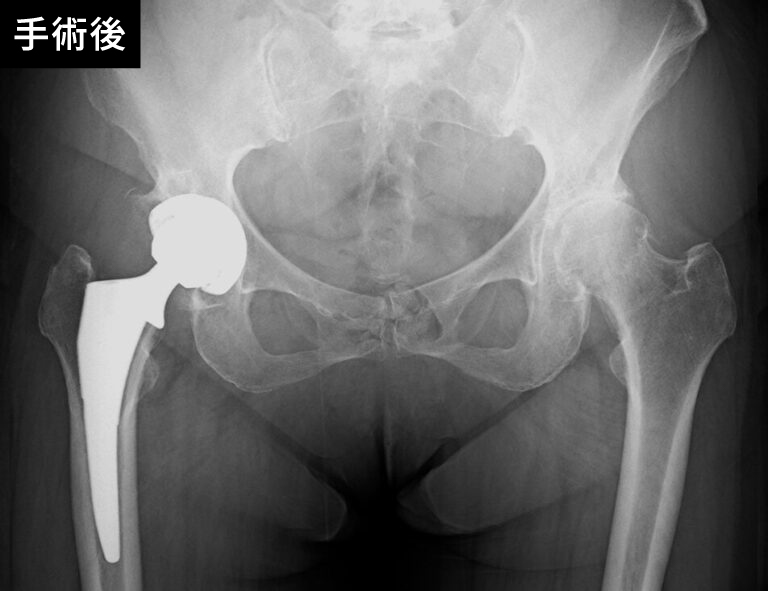

股関節の手術前後

手術の種類には、関節全体を置き換える「全人工関節置換術」と、一部のみを置き換える「部分人工関節置換術」があり、患者さまの症状や状態に応じて選択されます。当院では、専門医が最新の技術を駆使して安全で精密な手術を行い、術後の回復を最大限にサポートします。